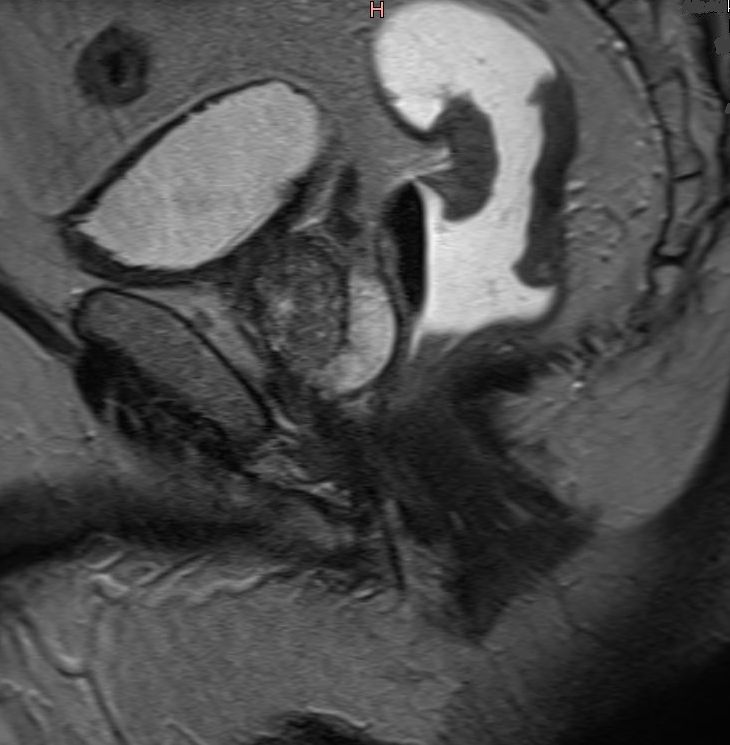

| Tumor | CT-Bild eines stenosierenden Rektumkarzinoms mit Infiltration der Hüllfaszie und Infiltration der Prostatakapsel. |

Frontalschnitt eines distalen Rektumkarzinoms im MRT. Der Tumor sitzt dem Sphincter unmittelbar auf.![]() | ||||||||||||||||||||||||||||||||||||||||||||||||||||||||